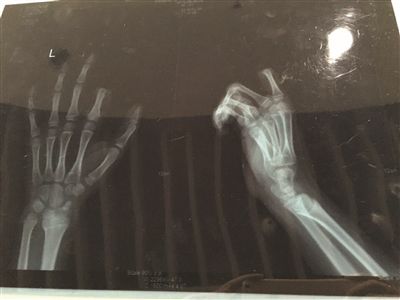

X光片显示孩子食指两个指节被切断。